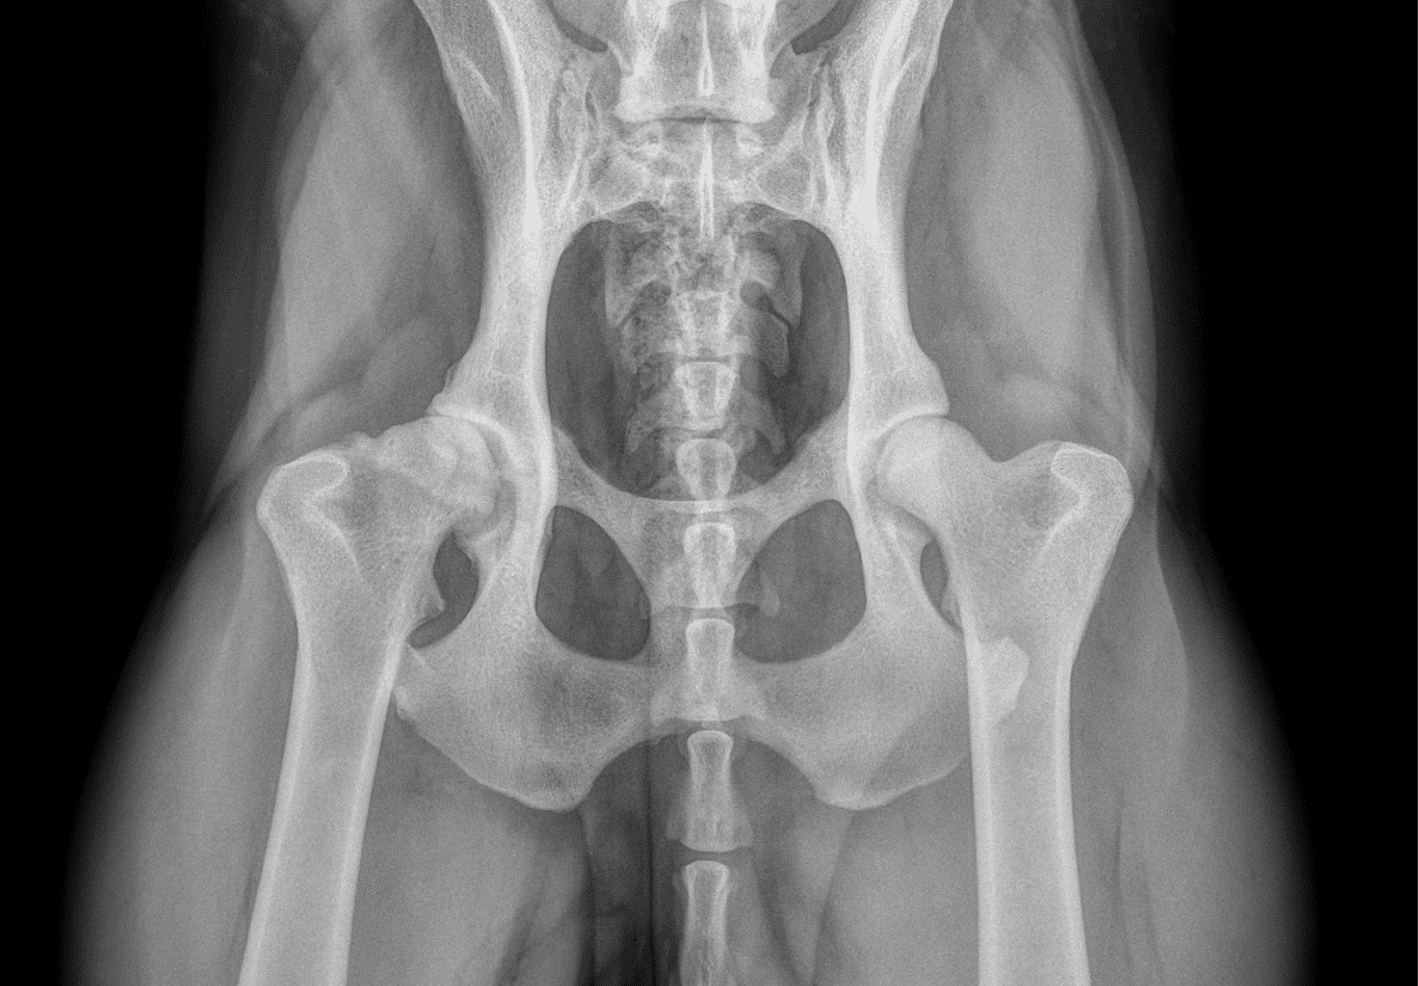

Dysplasie de la hanche chez le chien